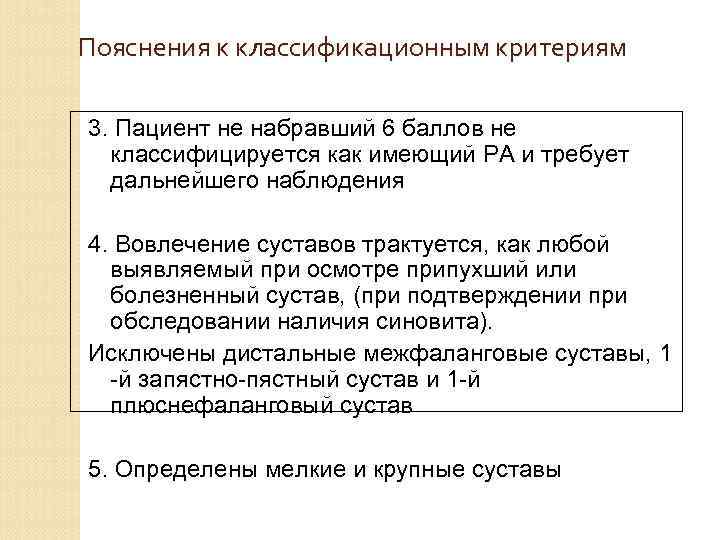

Пояснения к классификационным критериям 3. Пациент не набравший 6 баллов не классифицируется как имеющий РА и требует дальнейшего наблюдения 4. Вовлечение суставов трактуется, как любой выявляемый при осмотре припухший или болезненный сустав, (при подтверждении при обследовании наличия синовита). Исключены дистальные межфаланговые суставы, 1 -й запястно-пястный сустав и 1 -й плюснефаланговый сустав 5. Определены мелкие и крупные суставы

Пояснения к классификационным критериям 3. Пациент не набравший 6 баллов не классифицируется как имеющий РА и требует дальнейшего наблюдения 4. Вовлечение суставов трактуется, как любой выявляемый при осмотре припухший или болезненный сустав, (при подтверждении при обследовании наличия синовита). Исключены дистальные межфаланговые суставы, 1 -й запястно-пястный сустав и 1 -й плюснефаланговый сустав 5. Определены мелкие и крупные суставы